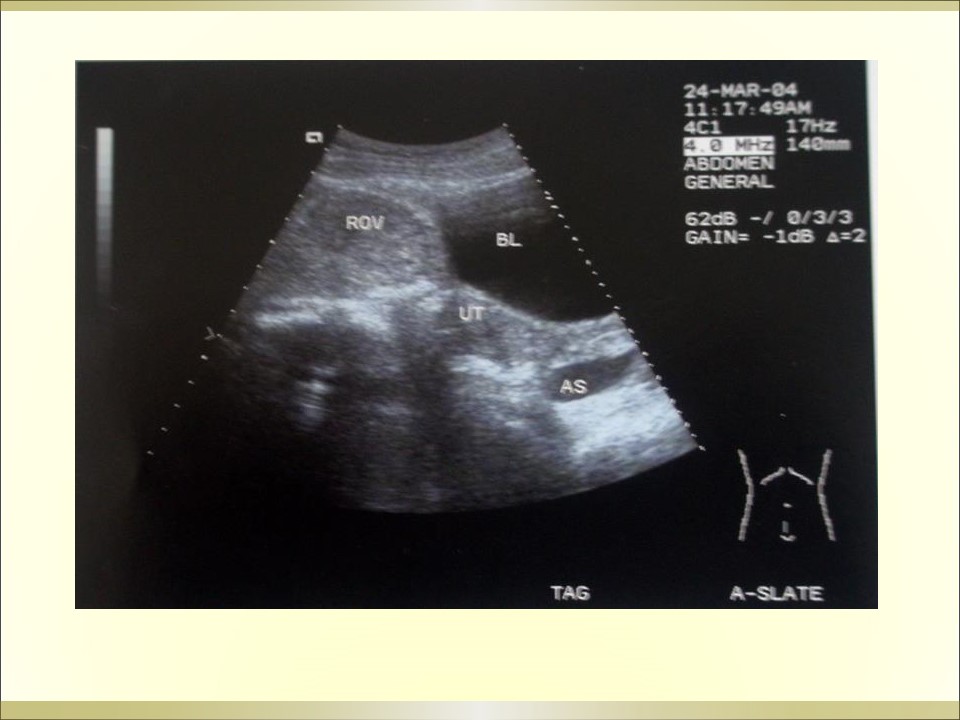

妇产科急腹症是指因妇科疾病引起的剧烈的急性腹痛,可以是原有疼痛突然加剧,或原无疼痛突然发生,是病因较多的常见病,特点是发病急、病变进展快、病情重,需要及时作出病因诊断及治疗。